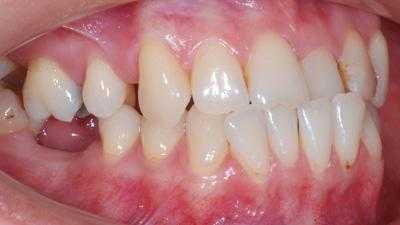

Завершенные клинические случаи дистального прикуса

Внутриротовые признаки

В полости рта дистальный прикус определяется по выступающим вперед верхним фронтальным зубам. В норме, при ортогнатическом прикусе, верхние резцы перекрывают нижние примерно на 1/3. При дистальной патологии между верхними и нижними резцами образуется расстояние — «саггитальная щель».

Из-за непропорционально выдвинутой верхней челюсти, дистальный прикус можно определить по выпуклому или «птичьему» профилю. Нос и верхняя губа выступают вперед, нижняя губа западает. Подборок скошенный, непропорционально маленький, иногда со складкой — «вторым подбородком». При серьезной дистальной окклюзии (с большой саггитальной щелью) губы в расслабленном состоянии не смыкаются и рот всегда немного приоткрыт.